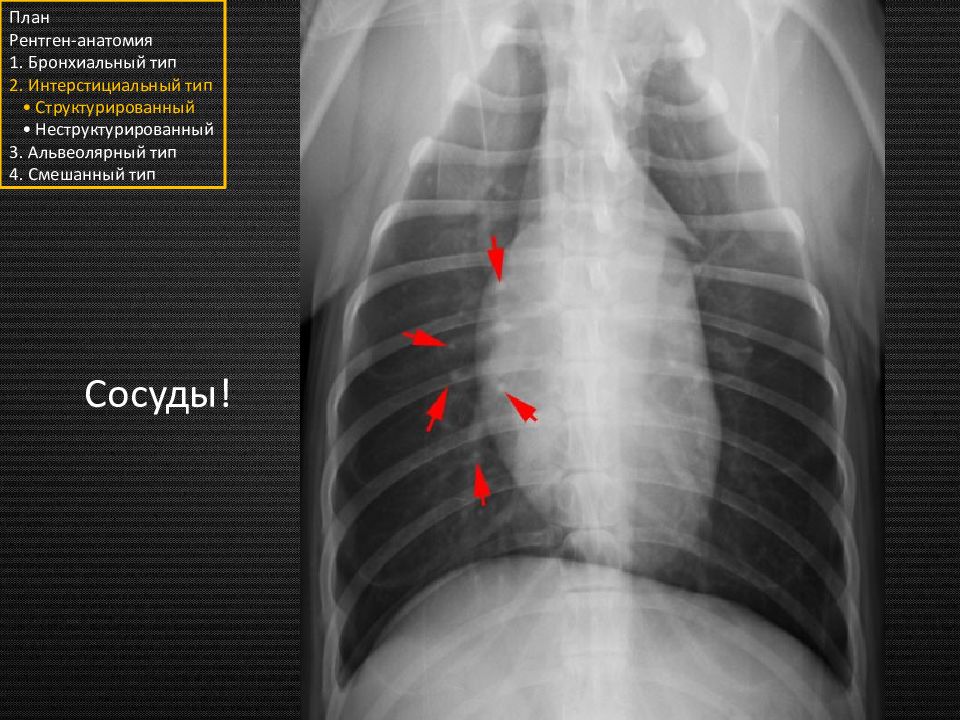

План Рентген-анатомия 1. Бронхиальный тип 2. Интерстициальный тип • Структурированный • Неструктурированный 3. Альвеолярный тип 4. Смешанный тип Сосуды!